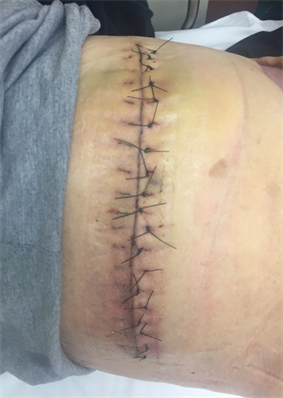

By hospital day (HD) 19, the patient’s wound bed had thick granulation tissue and was deemed suitable for split thickness skin grafts (STSGs). On HD 20, the patient underwent STSG to the right thoracoabdominal region, flank and hip followed by an interface of MepitelTM (Monlycke, Peachtree Corners, GA) and application of V.A.C. VERAFLOTM dressing (3M, Minneapolis, MN) for NPWT at −125 mmHg (Figure 3). The linear chest wound was closed primarily for 20 cm using single, interrupted 2-0 Nylon sutures (Ethicon, Bridgewater, NJ). After five days, the NPWT was removed revealing a 90% STSG take; the remaining open areas were treated daily with non-adherent gauze and ointment (Figure 4). The patient was discharged on HD 32 to a skilled nursing facility with close follow-up. The patient was seen in the clinic at two-week intervals, until the remaining open wounds were completely healed by week 4 following discharge (Figure 5 and Figure 6). At a subsequent admission four weeks later, the patient underwent a laparoscopic cholecystectomy with an interoperative cholangiogram which did not reveal any intraductal cholelithiasis.

Figure 5. Right chest wall with retained sutures four weeks post discharge (day 54). The sutures were removed in the clinic.